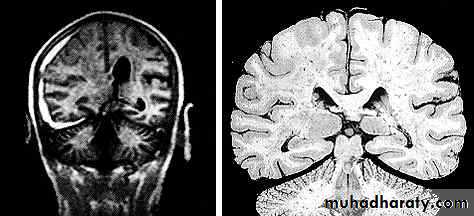

5. Hydrocephalus

a. Acutely due to obstruction of CSF outflow due to intraventricular blood.

b. Delayed post-traumatic communicating hydrocephalus due to impaired CSF reabsorption following traumatic subarachnoid haemorrhage

Intraventricular blood can lead to Hydrocephalus